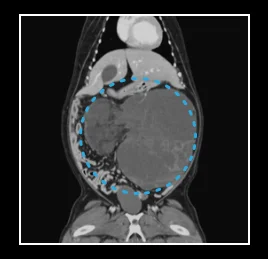

• 간 종양

• 비장 종양

• 신장 종양